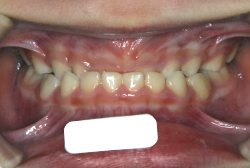

「歯並びの凸凹を直したい」という主訴で来院したケースです。診断の結果、たしかに「叢生」という隙間が足りないと言うことが原因の凸凹症例でした。

しかし、それ以上に問題なのは「前歯の噛み合い方が深すぎる」という症状で、初診の歯の正面写真を見ると下の前歯が全く見えません。こういう症状を矯正学では「過蓋咬合(かがいこうごう)」と言います。過蓋咬合を放置すると、将来的に顎関節に悪影響を与えるとされており、顎関節症の原因因子の一つです。また下の前歯の先端が、上の前歯の裏側の歯茎と強く接触するため、歯周病の原因にもなります。

検査の結果、凸凹が軽症なため非抜歯で矯正すること可能と判断、マルチブラケット装置にて治療しました。治療後は歯並びが綺麗になっただけでなく、噛み合わせ的にも正しい状態が確立しています。